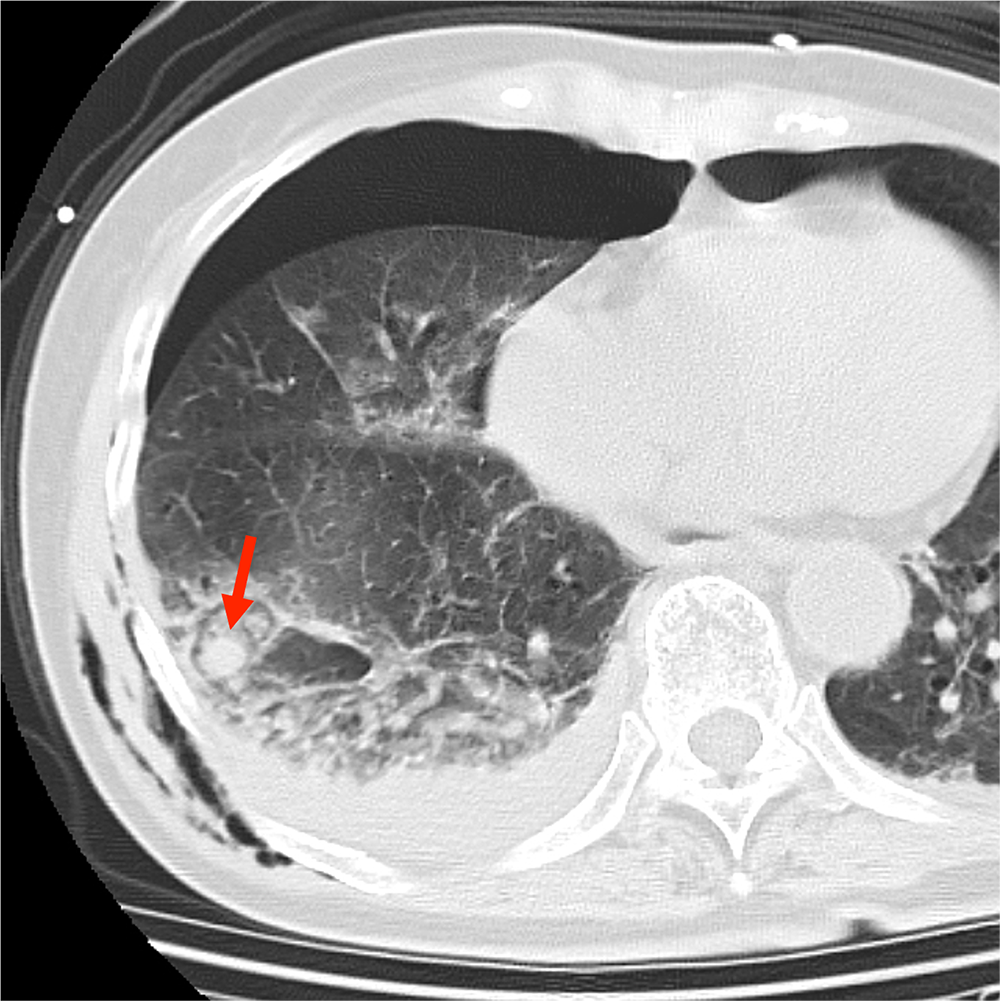

CTでは多発肋骨骨折、外傷性血気胸、肺挫傷、胸壁内気腫が認められた。

挫傷した肺内には結節状構造がみられ、肺気瘤の形成が示唆される。造影CTではこの内部に点状の濃染影が認められ、肺実質内血管外漏出(extravasation in the lung:EVIL)が疑われた。